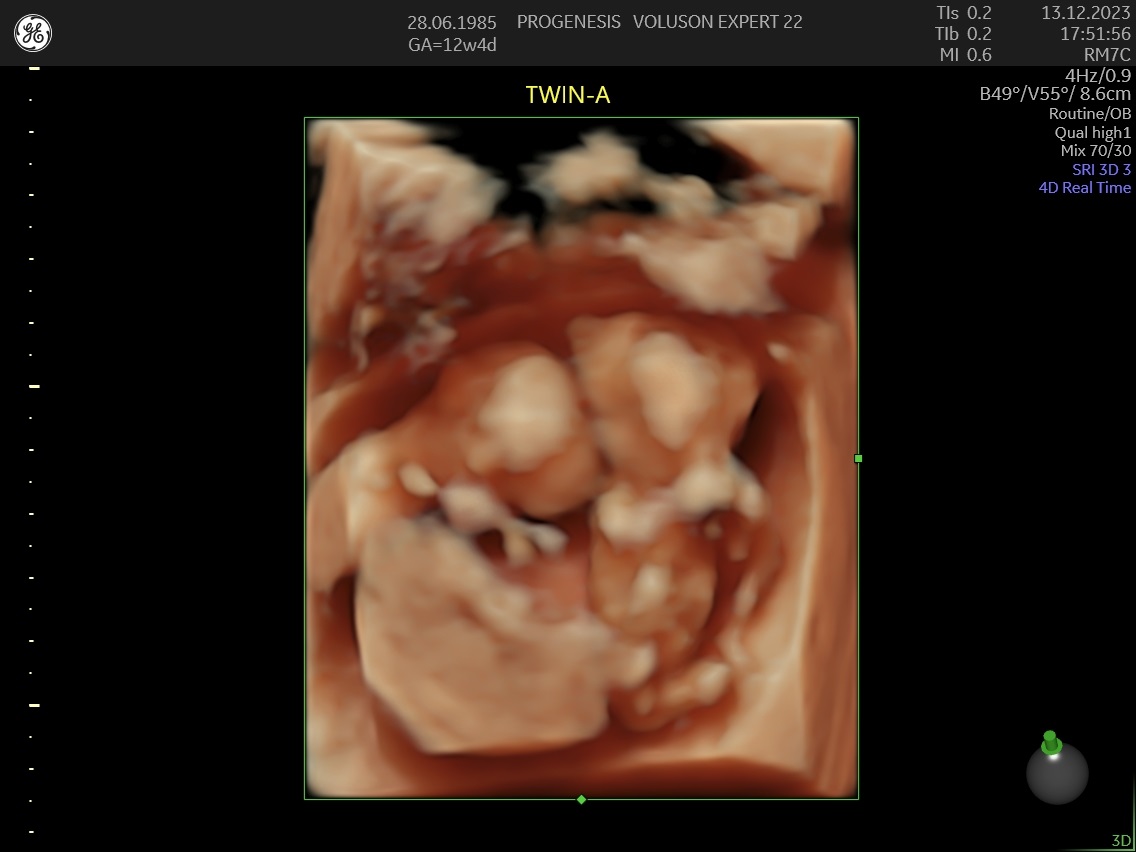

3D/4D LIVE Υπερηχογράφημα

Το 3D/4D LIVE είναι μια νέα τεχνολογία υπερήχων που δημιουργεί εικόνες του εμβρύου σε τρισδιάστατο ή τετραδιάστατο χώρο. Οι εικόνες αυτές είναι πιο ρεαλιστικές από τις παραδοσιακές εικόνες υπερήχων και δίνουν στους γονείς μια πιο ολοκληρωμένη εικόνα του μωρού τους.